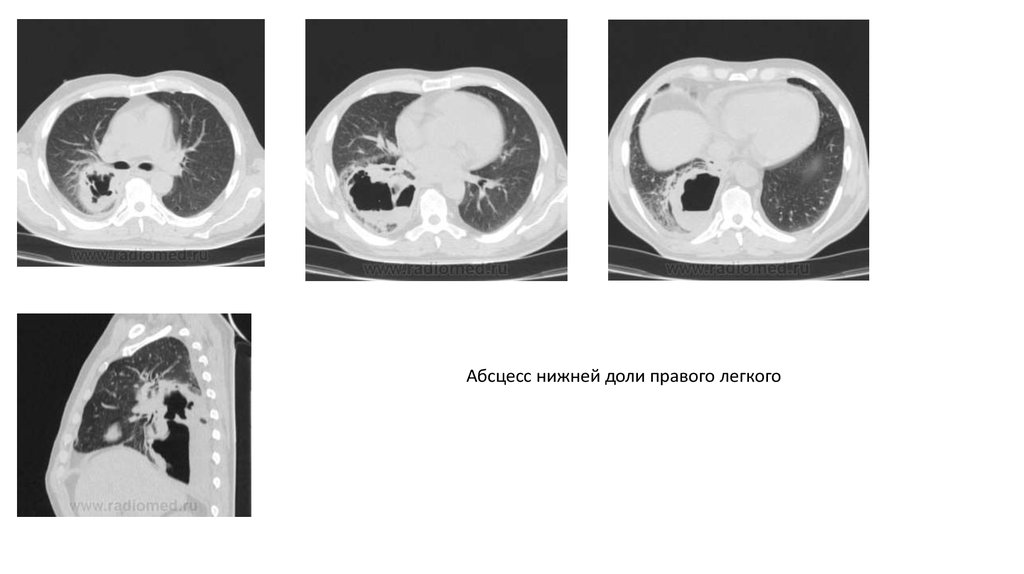

Абсцесс нижней доли правого легкого